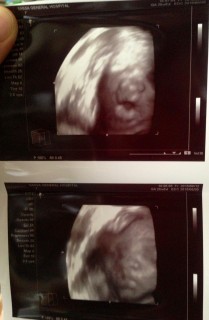

写真:28w5d:ちびちびさん:何度もまばたき

とても可愛らしいエコー写真が撮れました!

赤ちゃんはとても元気でエコーのときに手を顔にあてて可愛かったです!

ぱっちり目を開けててびっくり!何度もまばたきしてて可愛かったです(^_^)1377gmでした。